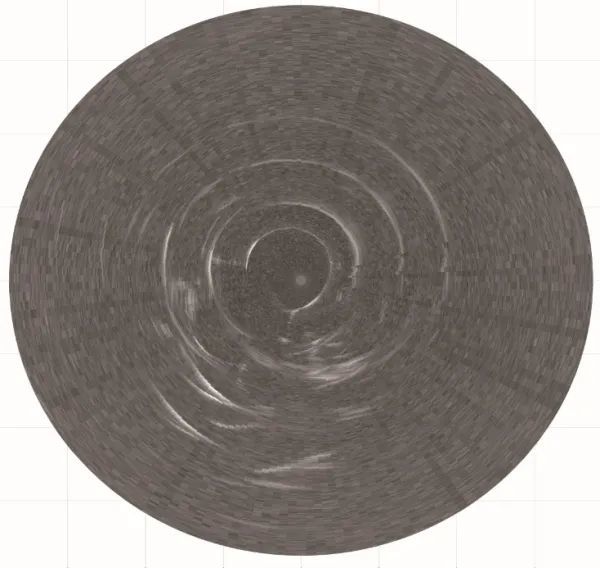

图1.自制多频超声内窥镜样品